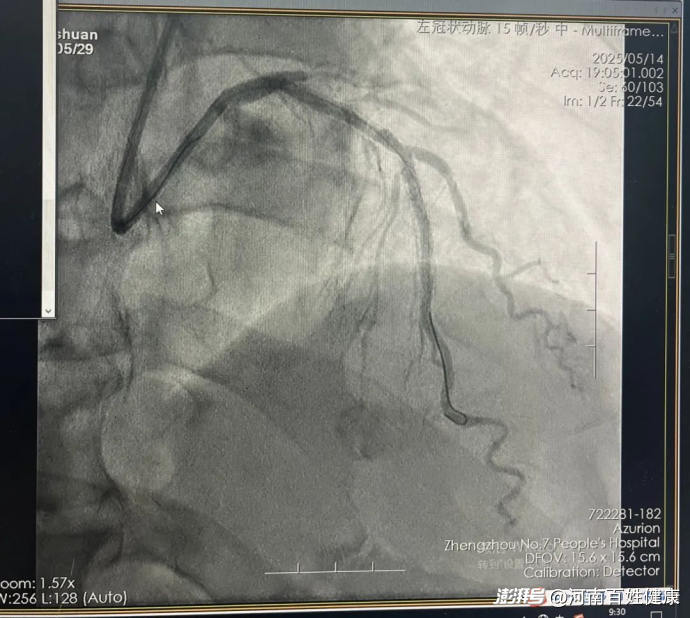

手术中,张杰主任凭借丰富的经验和娴熟的操作,将激光导管精准送至病变部位,仅用40分钟便成功打通血管,术后姜先生胸痛症状即刻缓解,次日即可下床活动。

(术后支架内无残余狭窄、血流畅通)